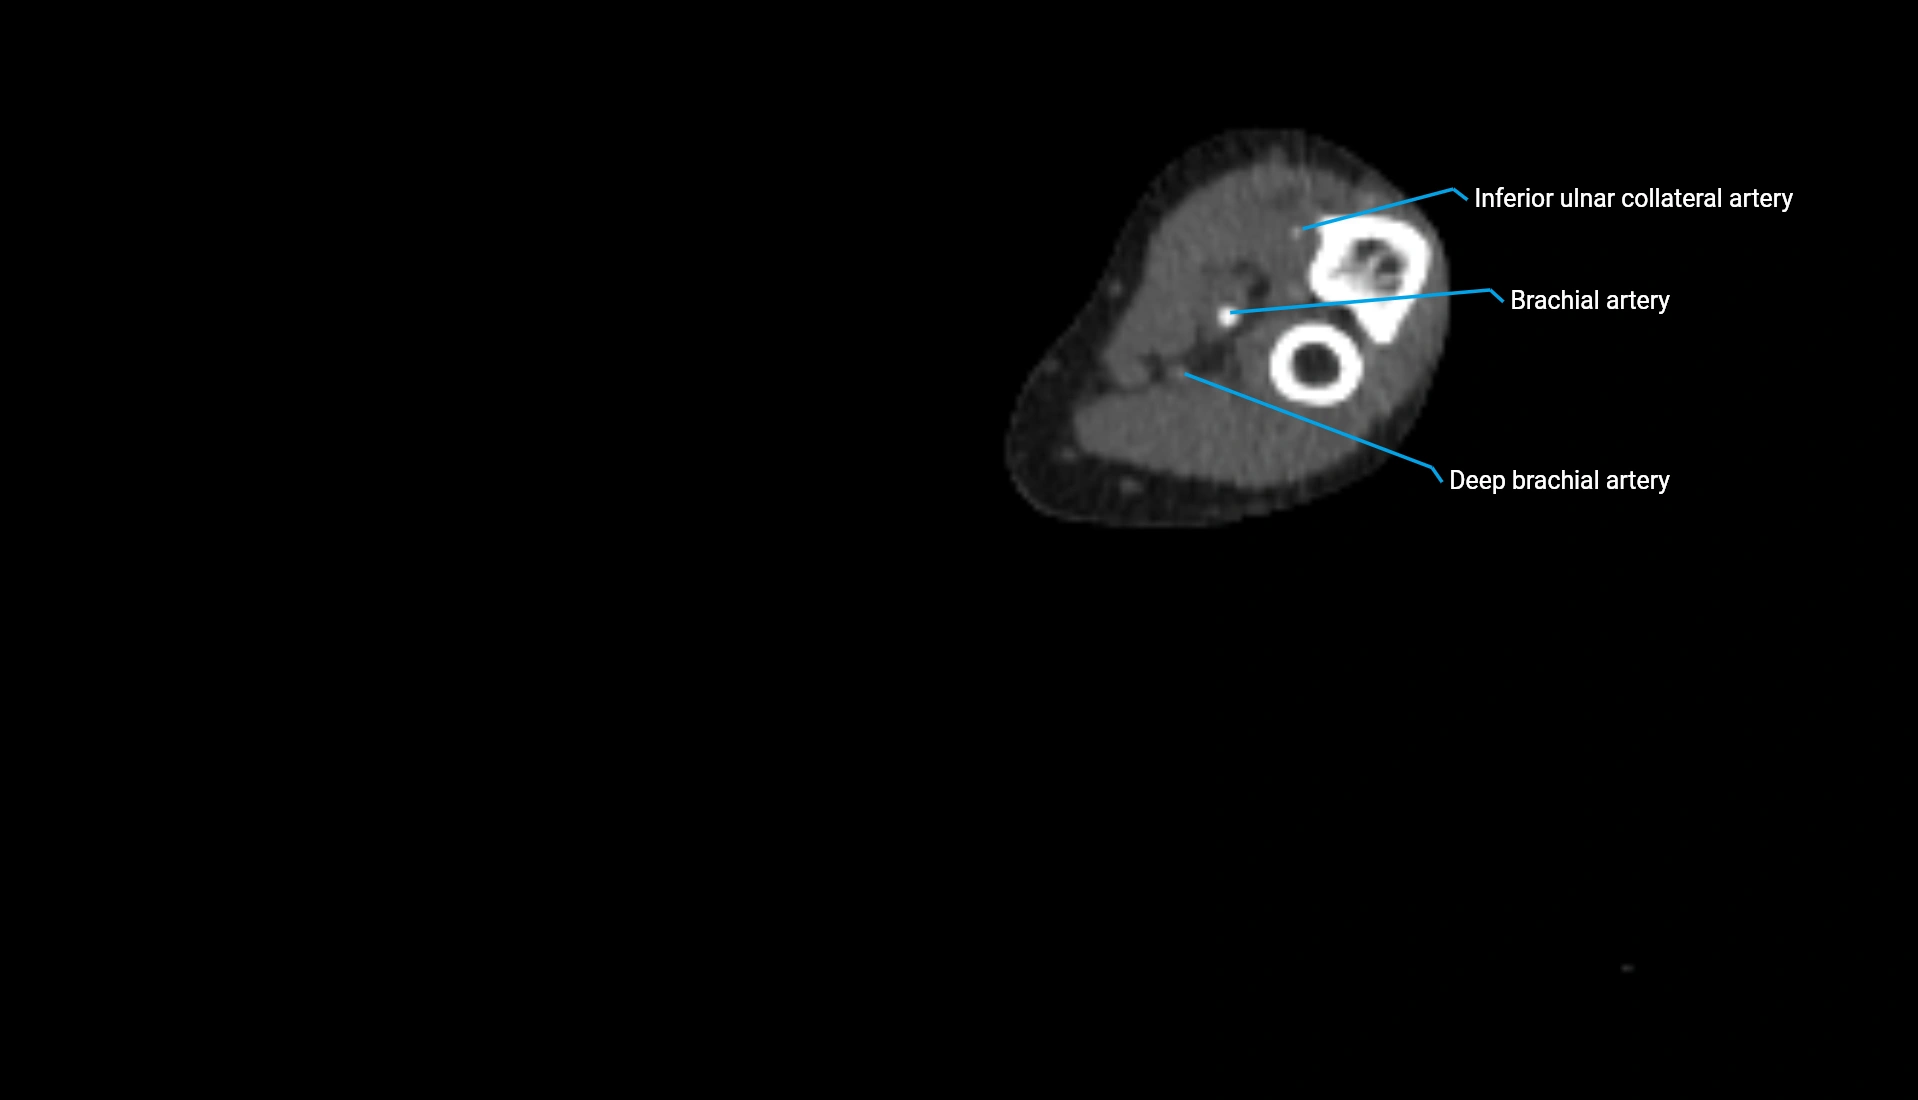

CT Appearance

Non-Contrast CT:

• Cortex: High-density, sharply defined

• Subchondral bone: Dense cancellous matrix

• Articular surface: Smooth concave contour articulating with the capitellum

• Excellent for evaluating bone integrity, alignment, and subtle fractures